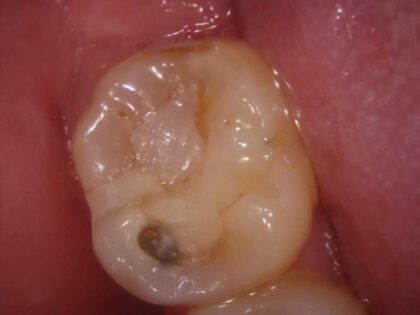

下のほうにとても深いむし歯があり、レントゲンでは神経に達していそうな感じがしたので、あらかじめ温存療法のお話しをしてから臨みました。

むし歯を検知液で染め出しながら慎重に除去していくと、案の定神経まで達し歯の中から出血が見られました。